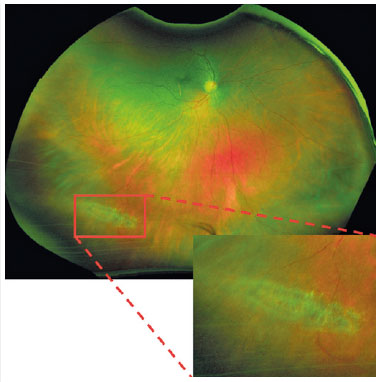

Решётчатая дегенера́ция сетчатки — чётко отграниченный неравномерно пигментированный овальный участок на периферии сетчатки, покрытый сетью облитерированных сосудов.

Офтальмоскопия. Для диагностики лучше подходят непрямая офтальмоскопия со склерокомпрессией и биомикроофтальмоскопия с высокодиоптрийными линзами или с линзой Гольдмана. Решётчатая дегенерация выглядит как чётко отграниченный вытянутый овальный участок, идущий параллельно зубчатой линии. Обычно расположен между экватором глазного яблока и зубчатой линией в верхнем или нижнем квадранте глазного дна. Участок покрыт сетью облитерированных сосудов. При осмотре в бескрасном свете по краю дегенерации можно увидеть фиксацию стекловидного тела, атрофические отверстия в сетчатке, начинающуюся отслойку сетчатки[1].